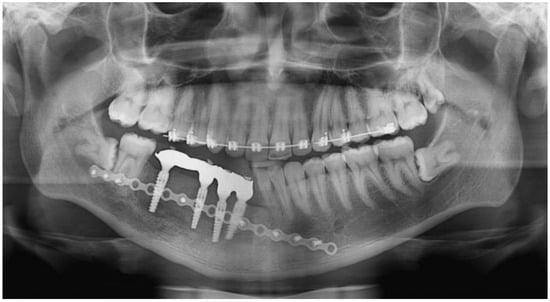

2.1. Case 1